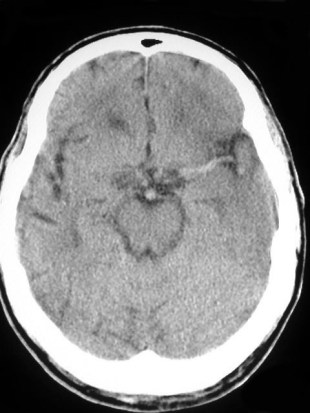

SIGNO DE LA ARTERIA CEREBRAL POSTERIOR HIPERDENSA

A la izquierda, hiperdensidad de ambas arterias cerebrales posteriores flechas). A la derecha, estudio a las 24 horas con infartos de los territorios de ambas cerebrales posteriores.

Es un signo precoz de infarto por obstrucción por trombo o émbolo que afecta a la circulación posterior cerebral. El significado de la imagen es el mismo que el de la arteria cerebral media hiperdensa, más conocido y frecuente.